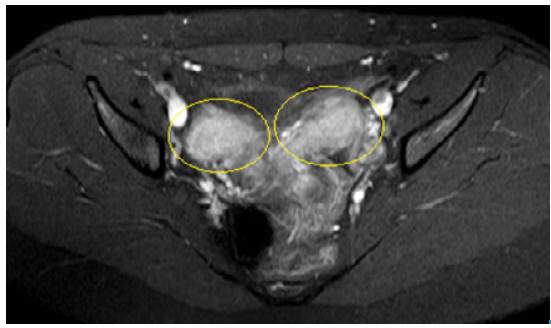

Antibiotic treatment was initiated with clindamycin (600mg every 6 hours) and intravenous gentamicin (240mg every 24 hours) for 7 days. Although dysthermia was not documented during hospital stay, magnetic resonance imaging was performed, revealing uterus didelphys and hematocolpos (Figures 3 and 4).

Cross-sectional magnetic resonance showing two uterine bodies.

Figure 4: Cross-sectional magnetic resonance showing two uterine bodies.

Source: Document obtained during the study.